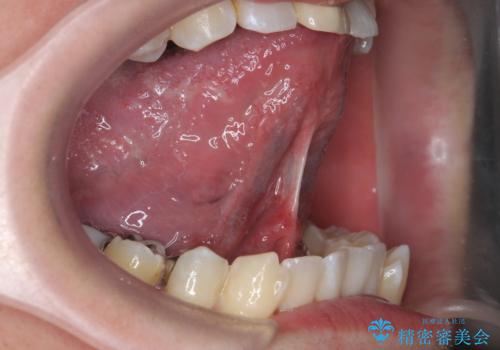

- メンテナンスでいらっしゃった患者様です。

歯を保護するためのナイトガードを装着していきます。

厚みのあるナイトガードを調整することで、夜間の歯ぎしりにより歯にかかる強い力を分散させることができます。